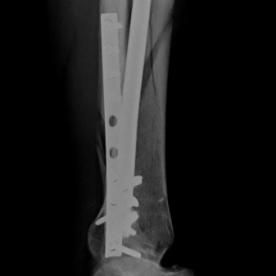

Röntgenbilder